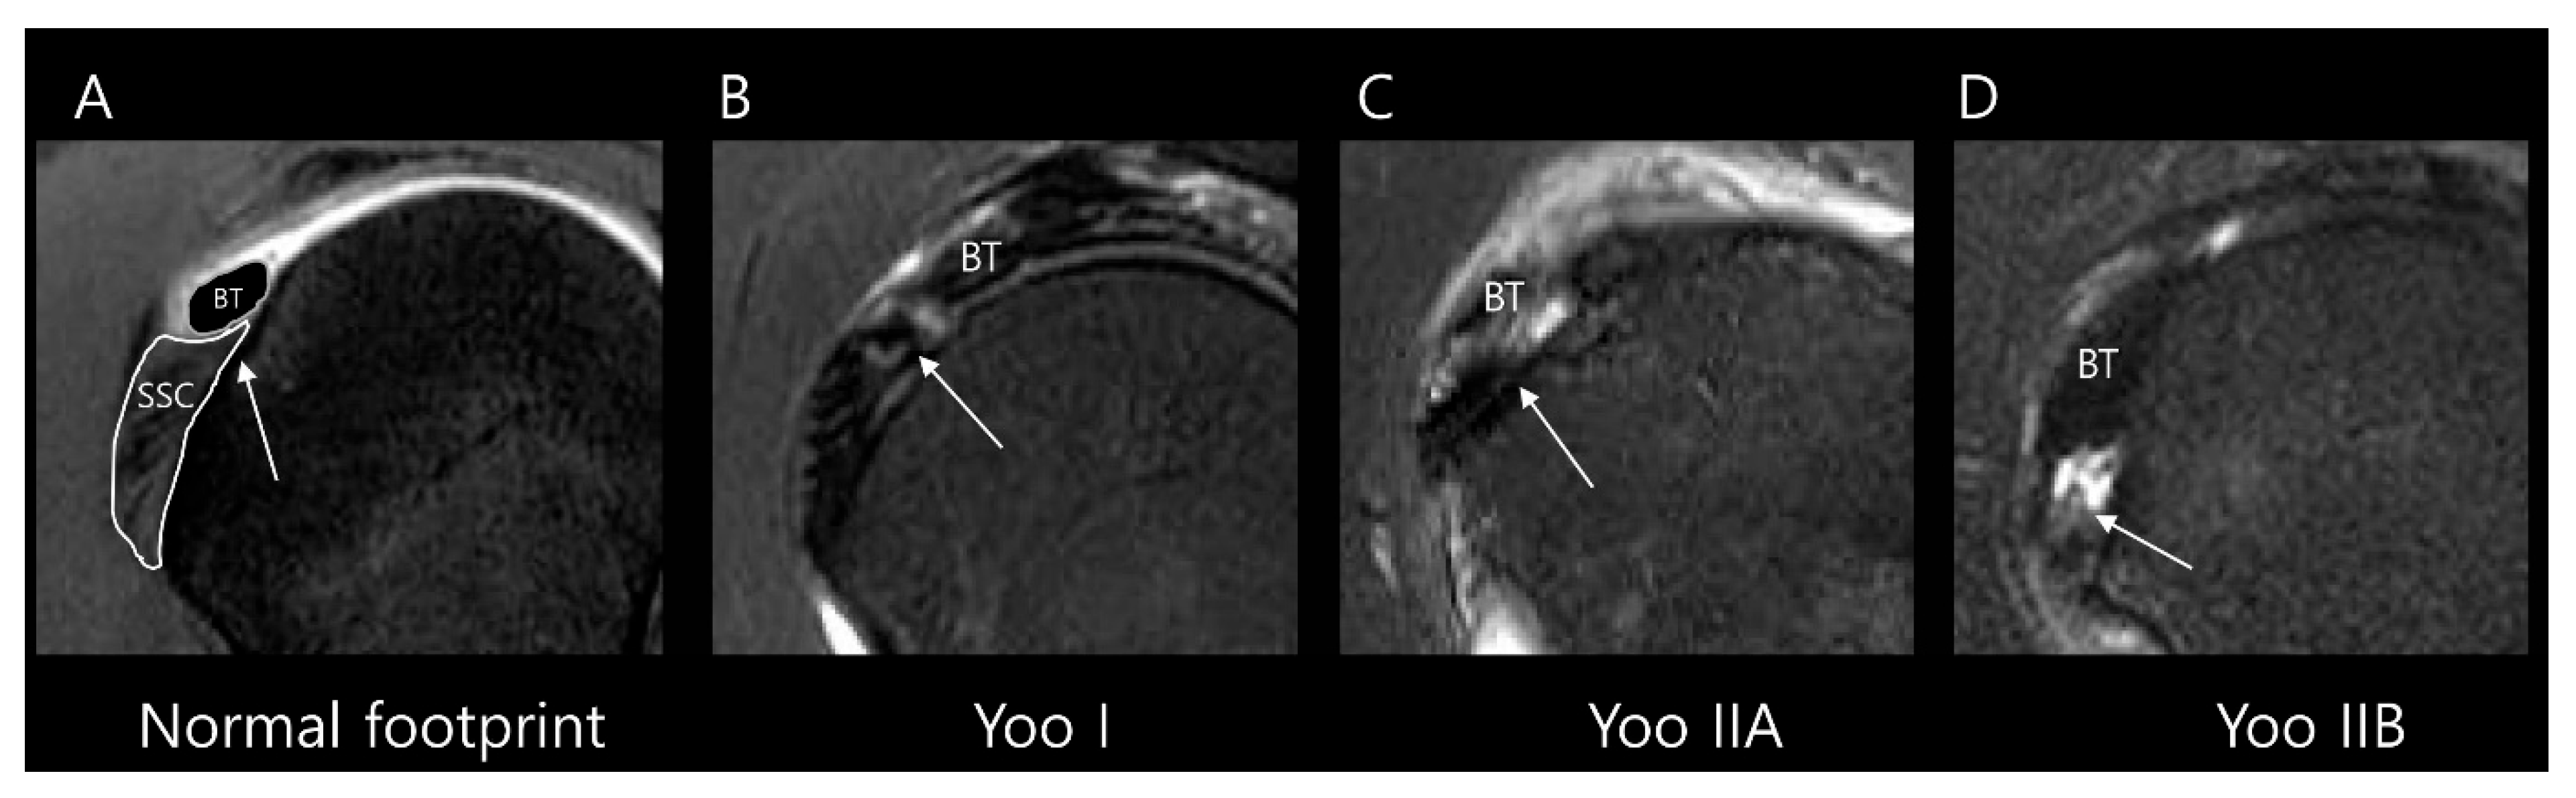

| Type I | Fraying or longitudinal split of the leading edge tendon |

| Type II | Partial detachment in the first facet (Lafosse type 1) |

| IIA | ≤50% detachment of SSC in the first facet |

| IIB | >50% detachment of SSC in the first facet without complete disruption of the lateral band |

| Type III | Complete first facet detachment with disruption of the lateral band (full thickness superior 1/3 of SSC tear, Lafosse type 2) |

| Type IV | First and second facets exposed with medial retraction of the subscapularis (equal to upper 2/3 of SSC tear, Lafosse type 3) |

| Type V | Complete SSC tear involving the muscular portion |

2.3. MRI Analysis

3.2. MRI Findings